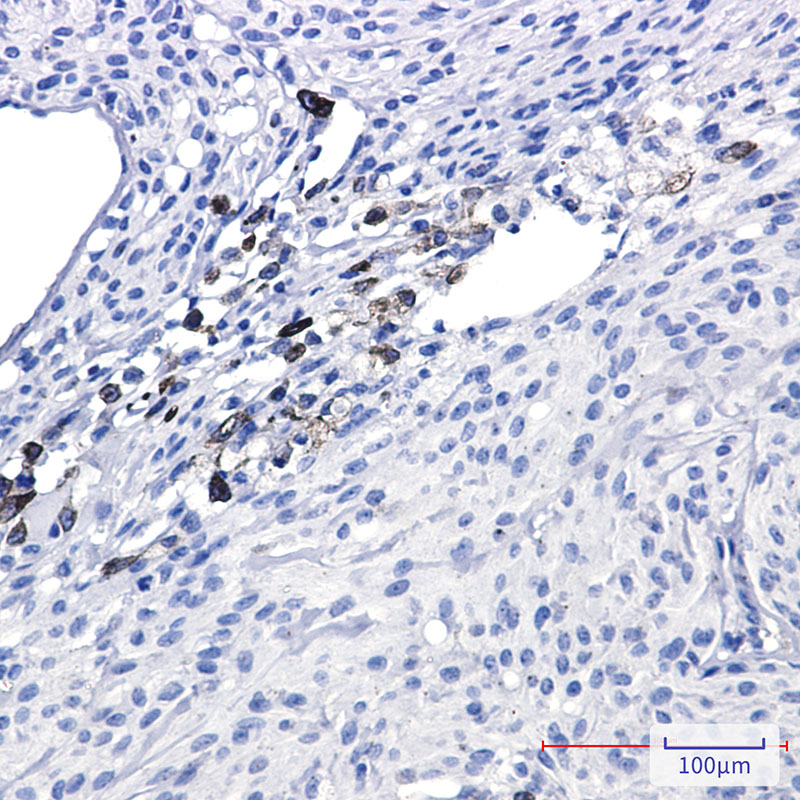

- Immunohistochemistry analysis of paraffin-embedded Human Brain using alpha Internexin antibody. High-pressure and temperature Sodium Citrate pH 6.0 was used for antigen retrieval.